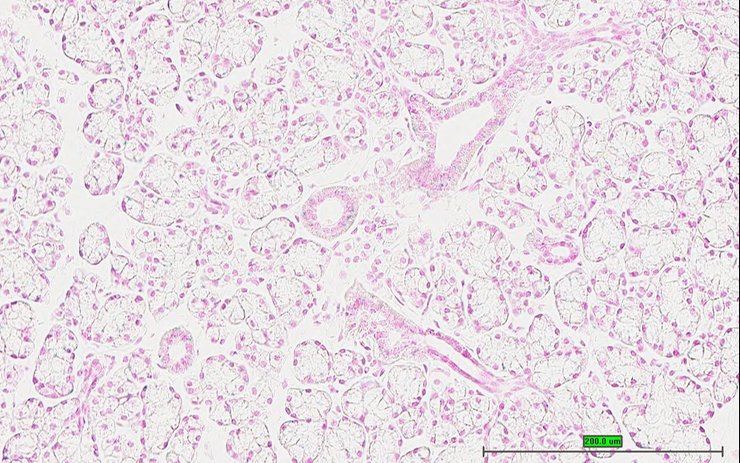

TS28: pituitary gland Present UC Davis_1879542

Specimen UC Davis_1879543: postnatal adult; Dlg5tm1b(EUCOMM)Wtsi/Dlg5+ (more )

Structure Level Pattern Image Note

TS28: spinal cord Present UC Davis_1879543